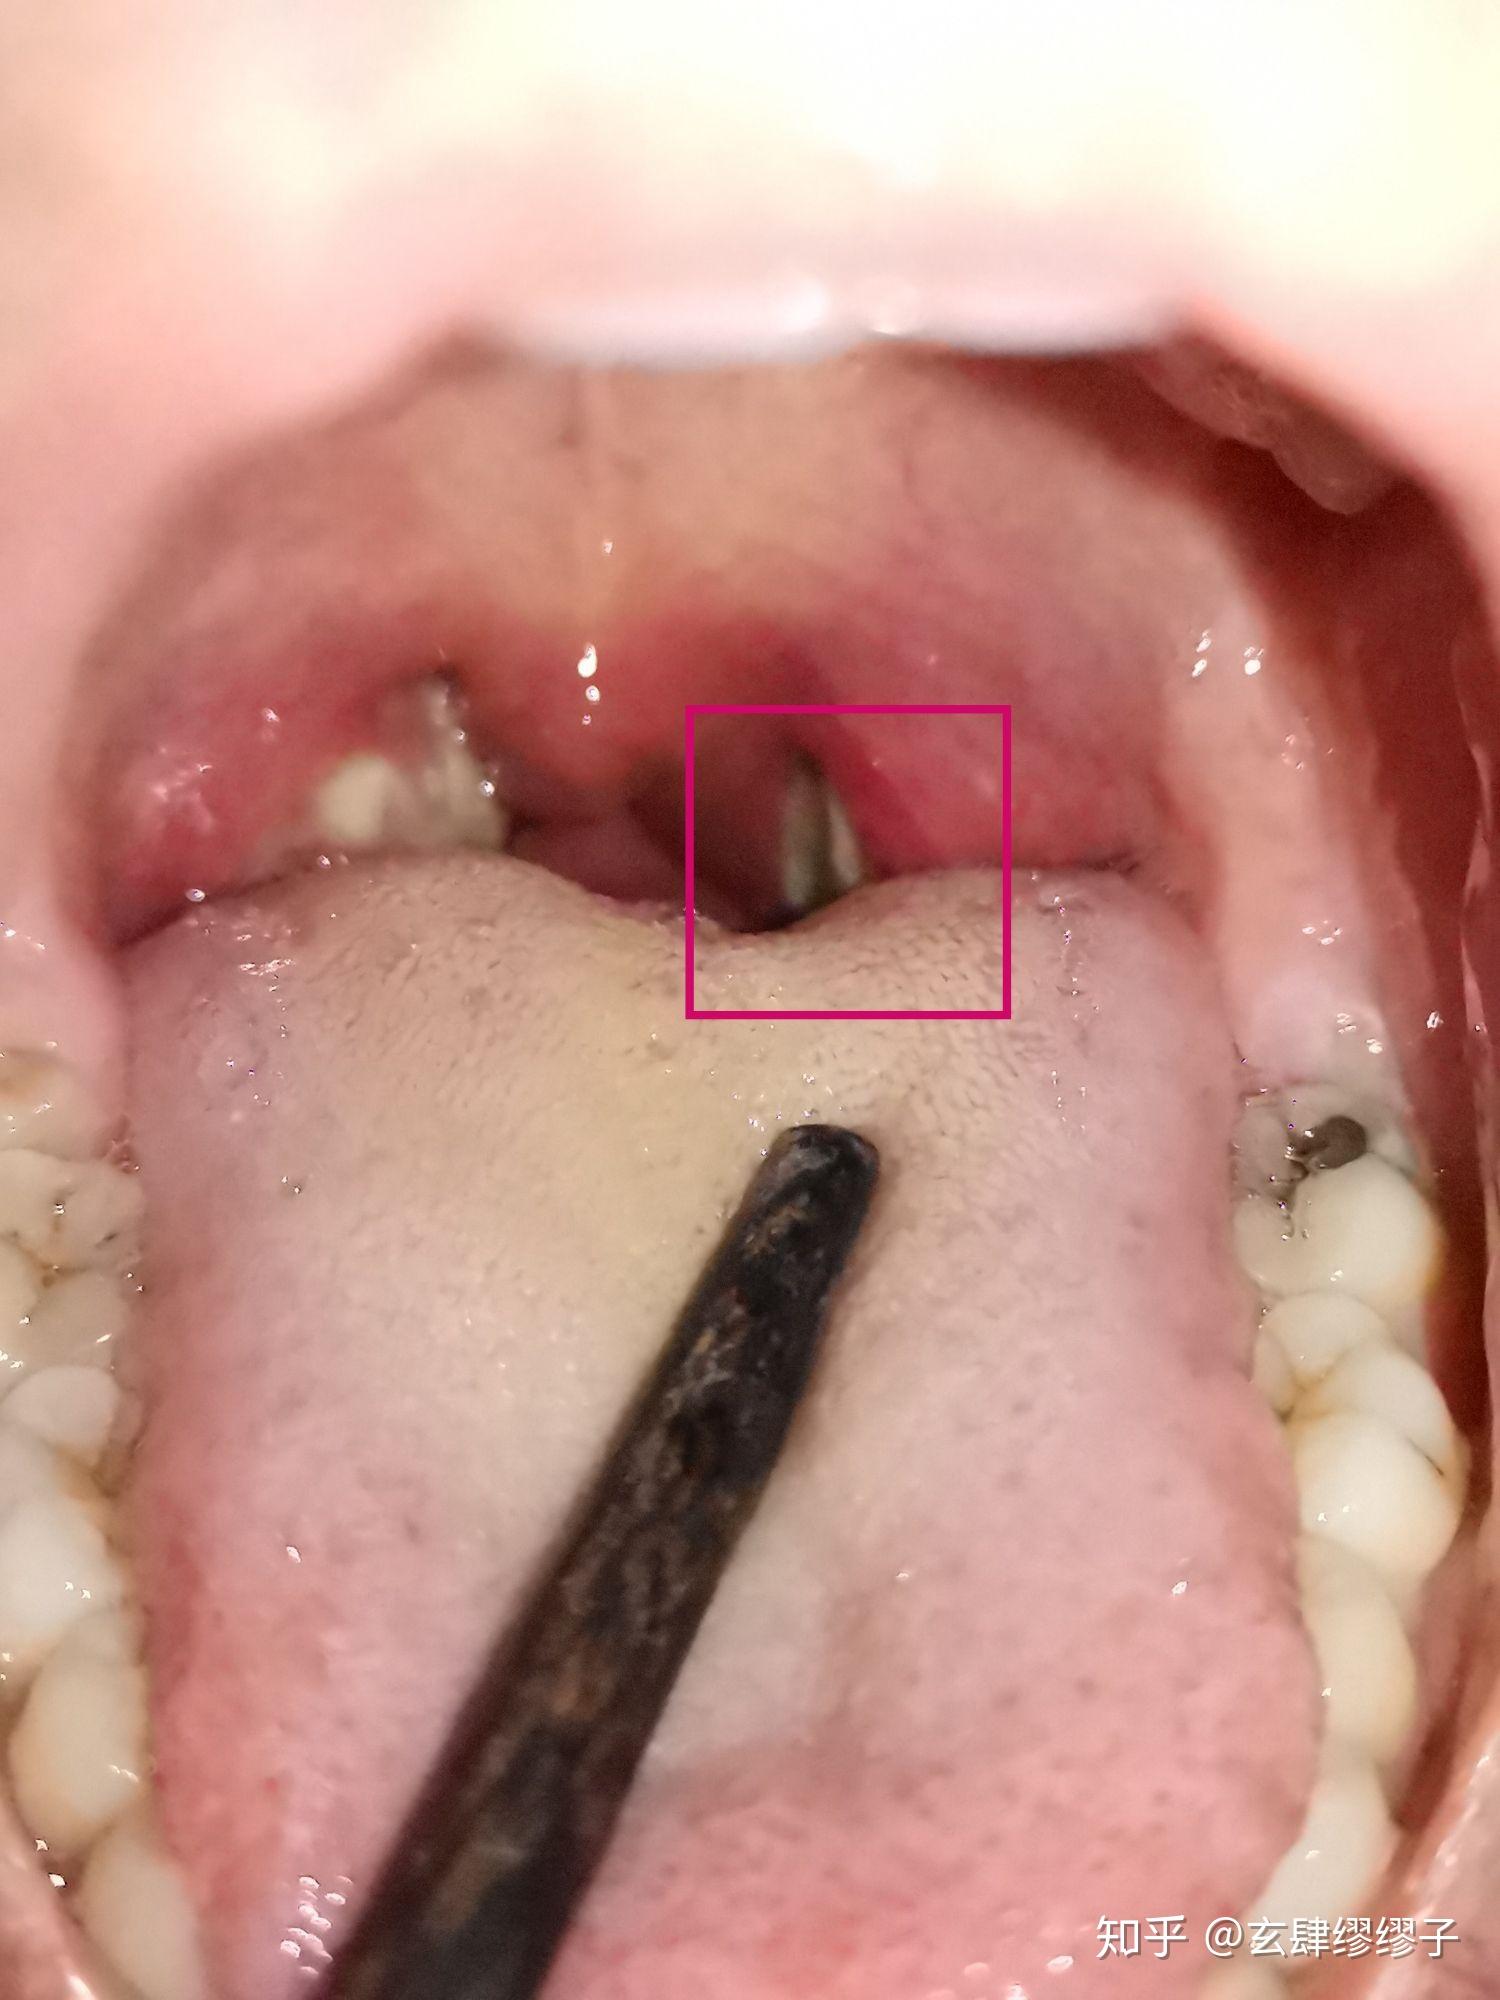

急性化脓性扁桃体炎患者的扁桃体红肿,表面有脓性渗出物

图片尺寸472x500